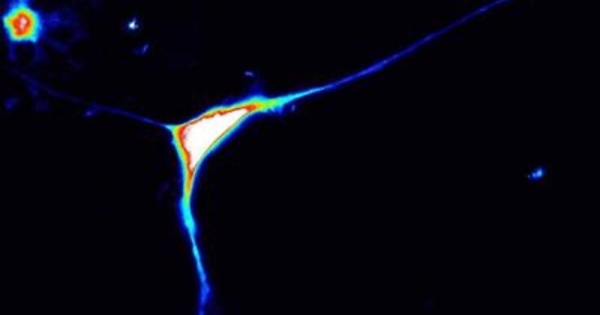

Torino, 13 gen. (Adnkronos Salute) - Importante passo avanti nella comprensione delle basi genetiche dell’autismo: Caprin1 è un nuovo gene responsabile di autismo. E’ quanto emerge dal Progetto NeuroWes di UniTo, uno studio multicentrico internazionale, coordinato da Alfredo Brusco, docente di Genetica medica del Dipartimento di Scienze mediche dell’Università di Torino e della Genetica medica universitaria della Città della Salute di Torino, sviluppato in collaborazione con l’Università di Colonia e recentemente pubblicato sulla rivista scientifica internazionale 'Brain'. Lo studio, basato sulle nuove tecnologie di sequenziamento del Dna e sullo sviluppo di modelli in vitro di cellule neuronali, ha permesso di dimostrare che mutazioni nel gene Caprin1 sono responsabili di alterazioni di specifici meccanismi neuronali che provocano dal punto di vista clinico una forma di disturbo dello spettro autistico. L’uso di tecnologie di sequenziamento dei geni umani, analisi dell’esoma ed analisi del genoma, hanno permesso, infatti, attraverso una collaborazione internazionale di identificare 12 pazienti colpiti da questa forma di disordine del neurosviluppo e comprenderne i meccanismi biologici associati. In particolare, il gruppo di ricerca del progetto NeuroWes, guidato da Alfredo Brusco e Giovanni Battista Ferrero del Dipartimento di Scienze cliniche e biologiche, si è dedicato dal 2015 allo studio della genetica dei disturbi dello spettro autistico, grazie alla collaborazione con molti gruppi italiani e dell’Autism Sequencing Consortium (Asc) alla Icahn School of Medicine, Mount Sinai di New York. L’analisi di centinaia di pazienti ha permesso di individuare un caso piemontese in cui era persa un’ampia regione di un cromosoma che comprendeva il gene Caprin1. Questa iniziale osservazione ha permesso di ipotizzare il ruolo di Caprin1 nella patogenesi dell’autismo e la successiva identificazione di 12 pazienti con una mutazione nel gene ne ha dimostrato il ruolo patogenico. I pazienti mostrano ritardo del linguaggio, disabilità intellettiva, deficit di attenzione ed iperattività, disturbo dello spettro autistico. L’autismo è un frequente disturbo del neurosviluppo che esordisce nei primi anni di vita e colpisce l'1% della popolazione nelle sue varie forme. E' caratterizzato da compromissione dell'interazione sociale, alterazione della comunicazione e interessi limitati, stereotipati e ripetitivi che impediscono di interagire adeguatamente con le persone e l'ambiente.